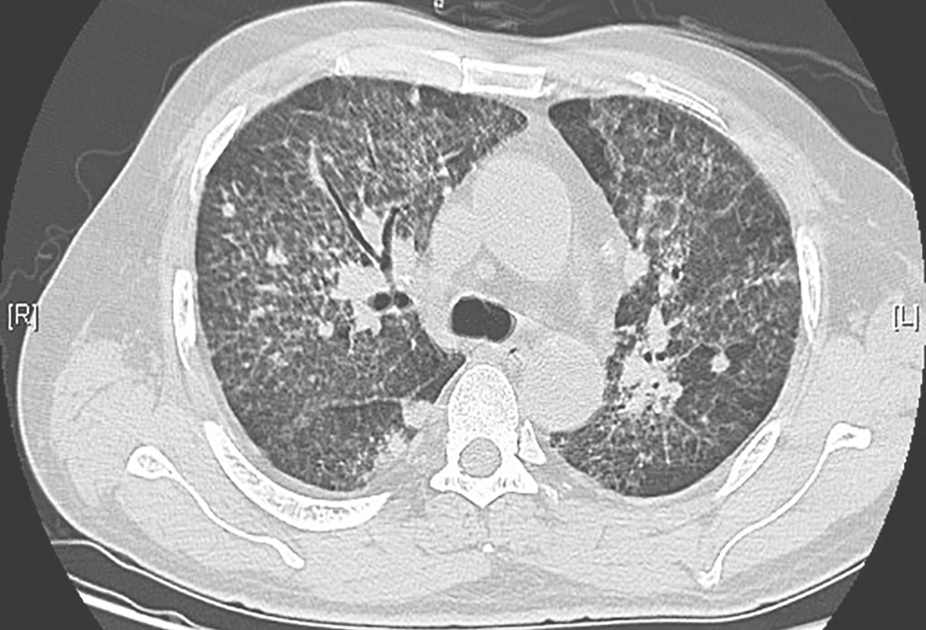

胸部CT:入院前3个月胸部CT示双肺弥漫性间质病变,可见磨玻璃和斑片高密度影,伴部分间质纤维化(图1)。予激素、抗感染及对症治疗后复查胸部CT,见双肺间质性病变较前增多。

图1胸部CT表现(2013-02-02)

发病初期,胸部CT见双肺间质弥漫性磨玻璃样渗出伴斑片高密度影,累及叶间裂